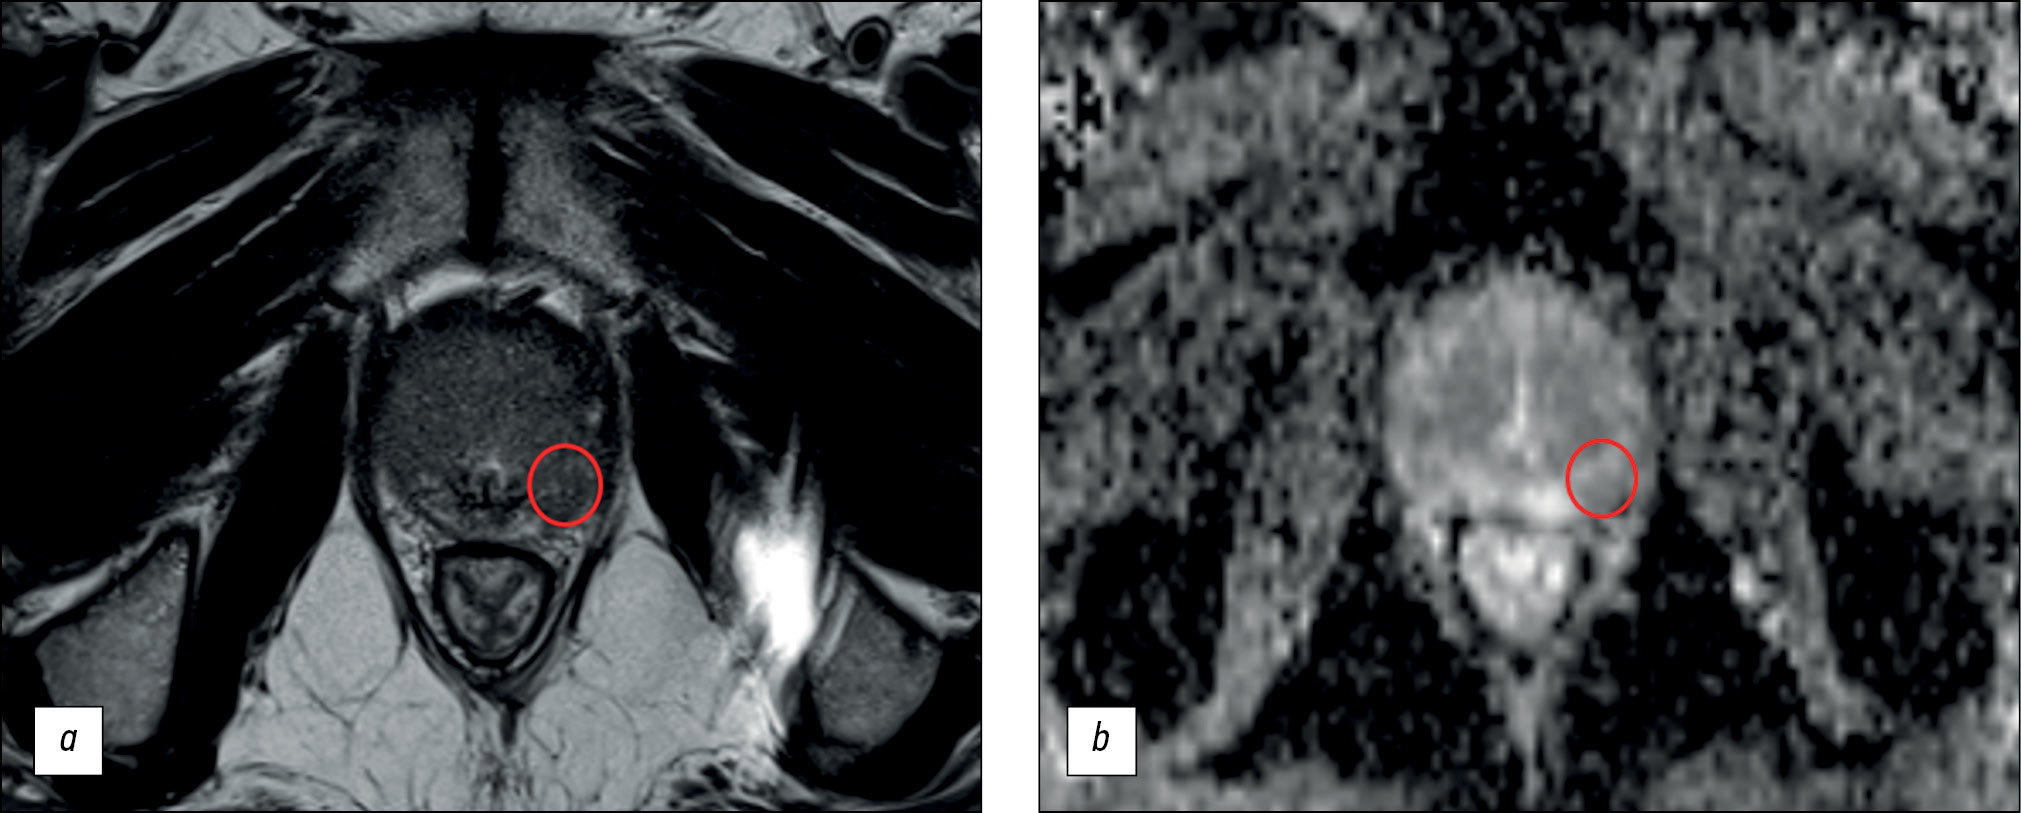

Comparison of multiparametric and biparametric magnetic resonance imaging protocols for prostate cancer diagnosis by radiologists with different experience

BACKGROUND: Magnetic resonance imaging can detect clinically significant prostate cancer and diagnose extracapsular extension and cancer stage. A scanning protocol that includes only T2-weighted and diffusion-weighted images represents a viable alternative to multiparametric magnetic resonance imaging provided that the high diagnostic accuracy of the test is maintained. In recent studies, biparametric and multiparametric magnetic resonance imaging demonstrated slight differences in the diagnostic accuracy in detecting prostate cancer.

AIM: To compare the diagnostic accuracy of biparametric and multiparametric magnetic resonance imaging for the detection of clinically significant prostate cancer using PI-RADS v2.1 with magnetic resonance imaging-guided multifocal biopsy as the gold standard.

MATERIALS AND METHODS: This retrospective study initially processed the medical records of 126 patients. The inclusion criteria were as follows: presence of PI-RADS 2.1 multiparametric magnetic resonance imaging, clinical information on free and bound prostate-specific antigen blood levels, a multifocal prostate biopsy performed, and a time interval between magnetic resonance imaging and biopsy of no more than 14 days. Three investigators (radiologists with <2, 2–5, and >5 years of experience) independently evaluated biparametric magnetic resonance imaging of the prostate for the presence of pathological foci. After 2 weeks, the researchers evaluated the multiparametric magnetic resonance imaging dataset of the prostate. Each lesion detected, starting from PI-RADS category 3, was compared with the result of a multifocal fusion biopsy. The biopsy result was presented as a sum of Gleason scores, and a Gleason score of ≥7 was considered clinically relevant. According to magnetic resonance imaging data, findings meeting PI-RADS criteria 4 and 5 were considered tumor foci.

RESULTS: The best values of sensitivity and specificity of foci detection on magnetic resonance imaging of the prostate gland were 62.5% and 74.6%, respectively. The highest diagnostic accuracy achieved was 70.1%. Magnetic resonance imaging had higher specificity rates for detecting prostatic foci when interpreted by radiologists with 2 years and >5 years of experience.

CONCLUSION: Both biparametric and multiparametric magnetic resonance imaging of the prostate demonstrated suboptimal diagnostic accuracy. The sensitivity and specificity of the method tended to improve with increasing experience of the radiologist. Biparametric protocols of prostate scanning have a definite economic advantage over multiparametric protocols because of the absence of contrast agents and consumables and a significant decrease in magnetic resonance scanner loading time; however, their use can lead to a decrease in the diagnostic accuracy of the method.